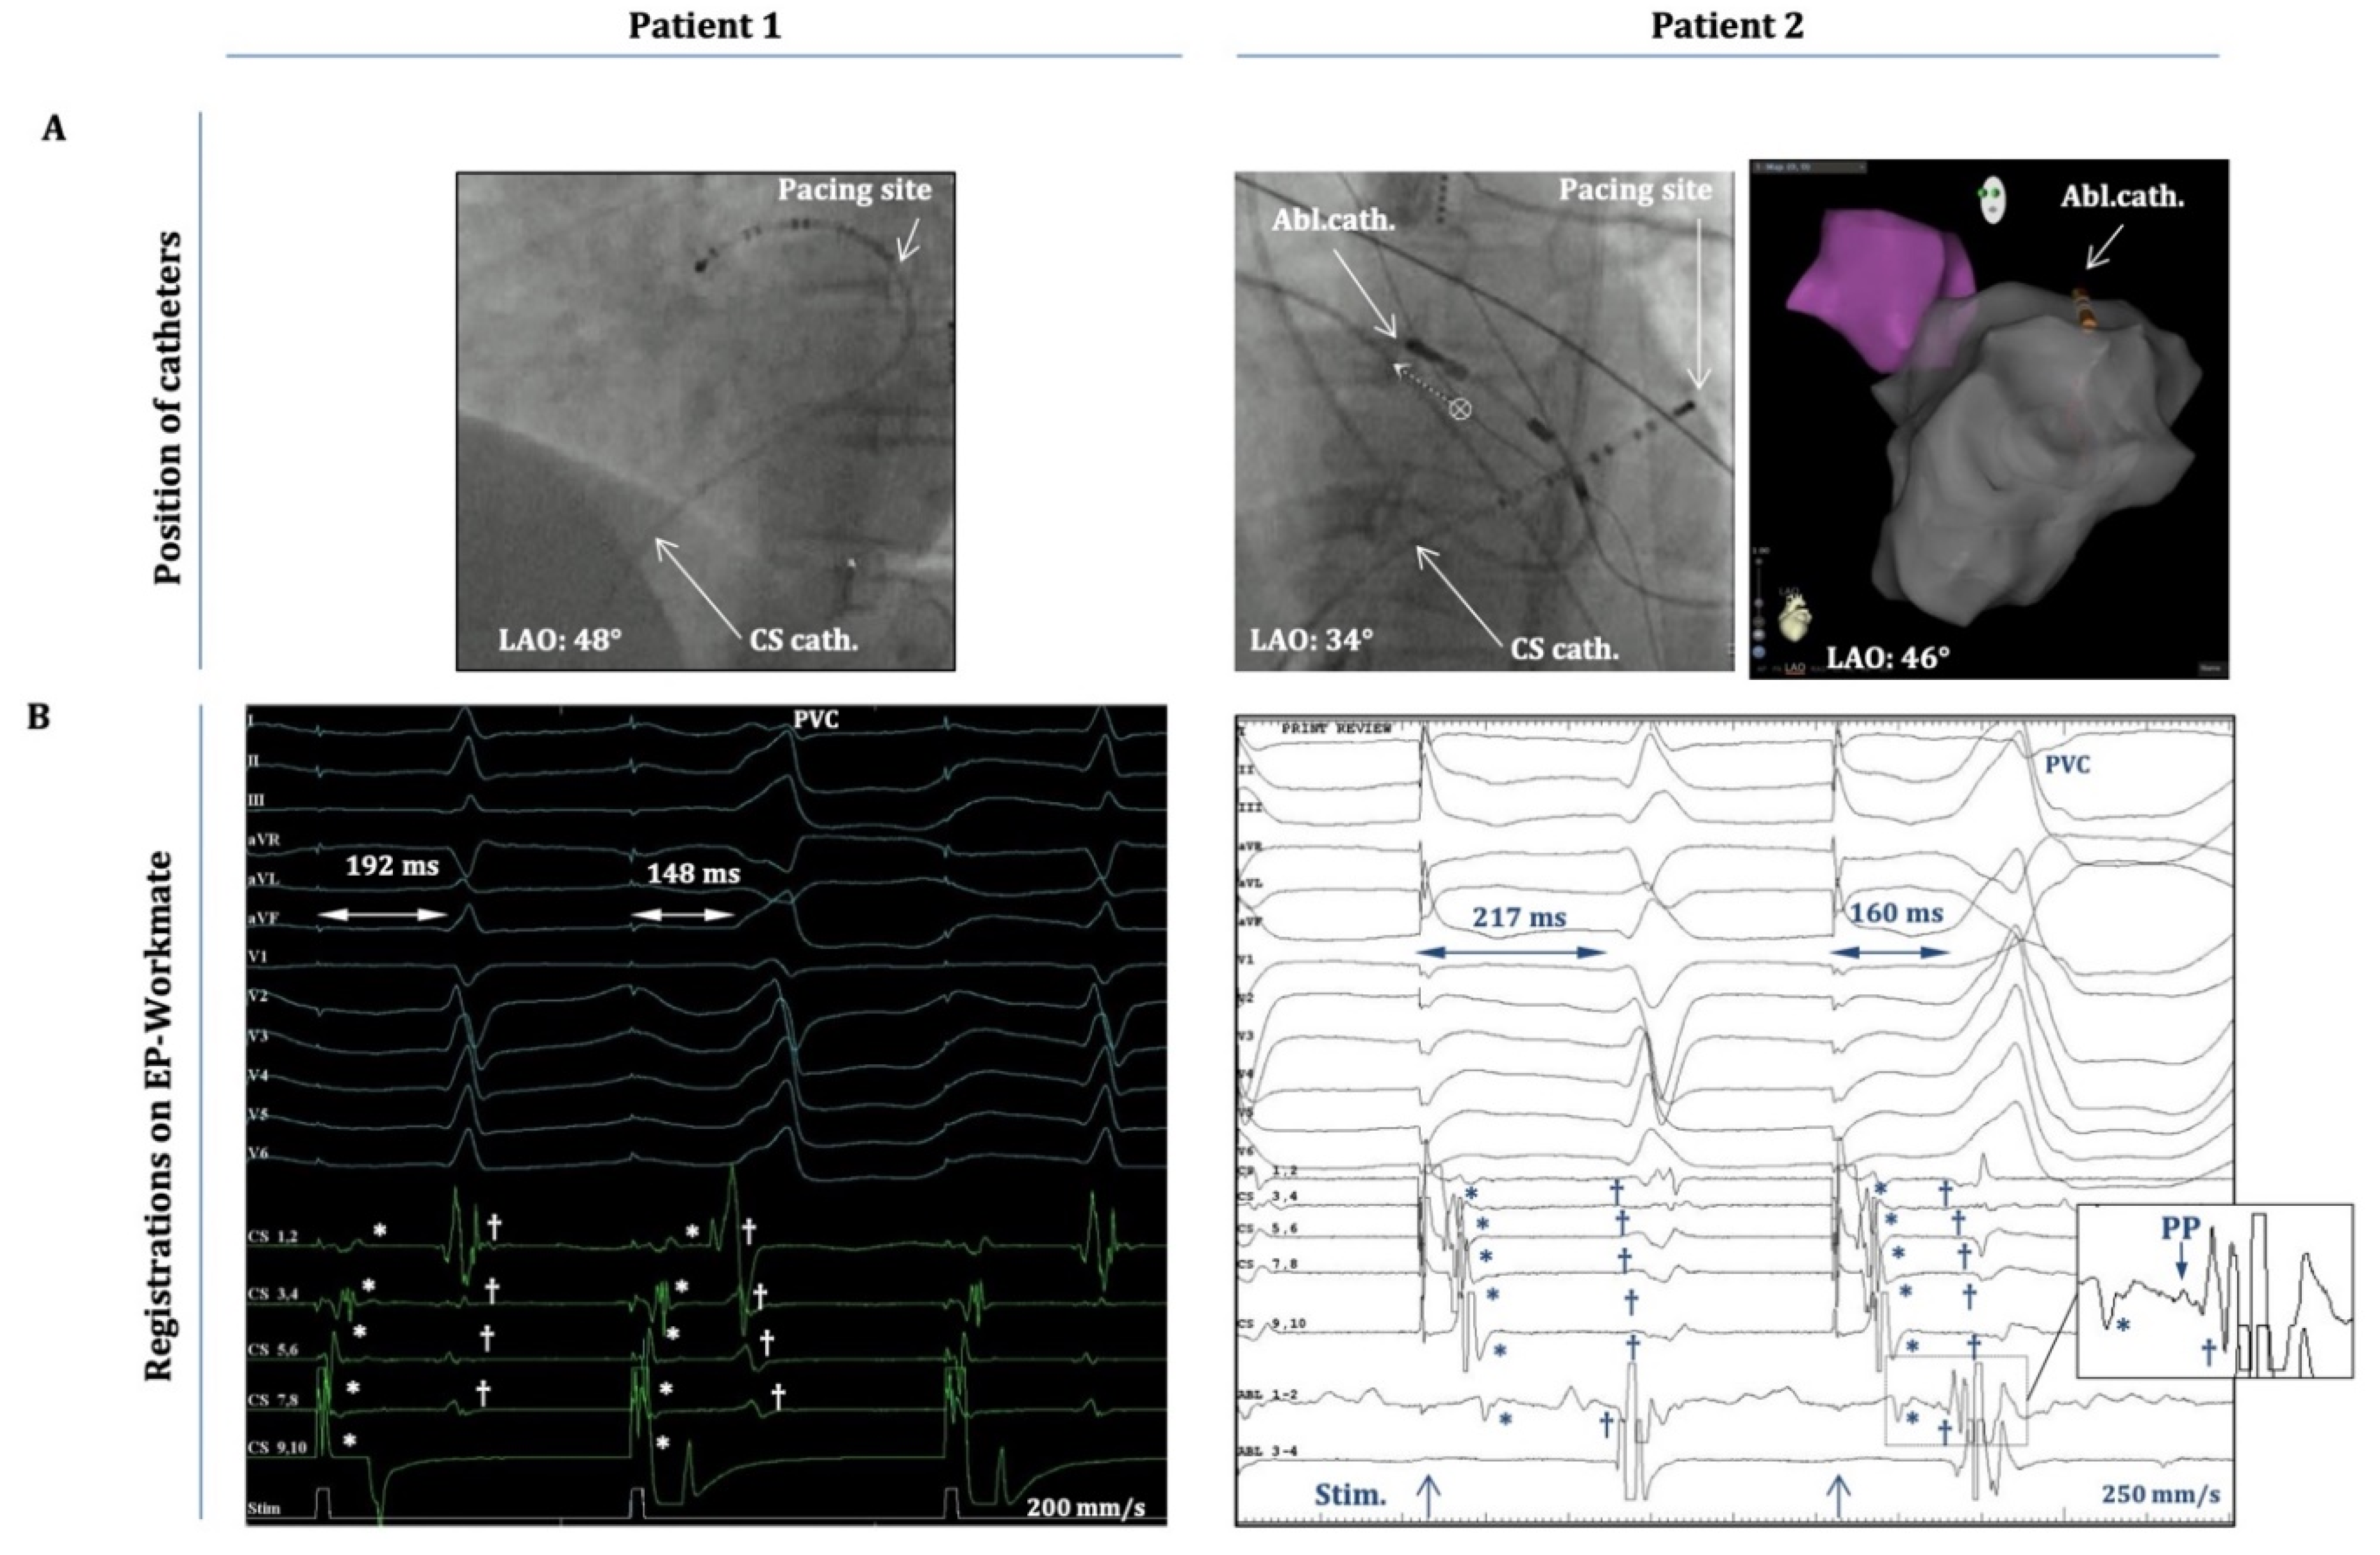

Figure 2.

Intracardiac electrograms (EGMs) during atrial-pace-induced PVCs. A) Positions of the decapolar catheter (CS) and the ablation catheter (Abl.) as depicted on fluoroscopy (LAO projection) and on the anatomical map of the CARTO system (in patient 2). Patient 1: the decapolar catheter is located in the distal CS/great cardiac vein, and pacing occurs from CS 9,10. Patient 2: decapolar catheter is located more proximally in the CS (CS 9,10 at CS-ostium), and the ablation catheter is at the superior mitral annulus/aorto-mitral-continuity; pacing occurs from CS 1,2. B) 12-lead EGMs and intracardiac EGMs from the decapolar/ablation catheters (the latter only for Patient 2.) as recorded by the EP-Workmate system during an atrial-pace-induced PVC. Timing of the pacing stimulus is depicted at the bottoms of each panel. The “atrial-stimulus-to-normal-QRS time” and the “atrial-stimulus-to-PVC time” are depicted on both recordings. Note: “stimulus-to-PVC time” is shorter in both cases than the “stimulus-to-normal-QRS time”. *Represent the atrial activation signals and † designate the ventricular activation signals on both panels. Inset) Magnified image of the framed part of the EGM on „Abl1-2” depicting the atrial (*) and ventricular (†) activation signals and a (putative) pre-potential (PP) between them.

Importantly, these PVCs occurred after apparent atrial capture, hence they were not elicited by inadvertent ventricular capture. This is clearly shown in

Figure 2, which demonstrates (case 1 and 2), that the atrial activation sequence on the decapolar electrodes (within the CS) occurs before the onset of the „atrial-pacing-induced” PVC, during pacing from CS 9-10 (case 1) or from CS 1-2 (case 2). It is also evident that there is an isoelectric line between the atrial and ventricular local activation signals. In addition, for case2 (inset in Figure2.B) a small pre-potential between the atrial and ventricular signals on Abl1-2 could also be appreciated (with the ablation catheter located at the spot of earliest ventricular activation). Moreover, the „atrial-stimulus-to-PVC-interval” (from the atrial pacing stimulus till the PVC-onset) was consistently shorter than the „atrial-stimulus-to-normal-QRS-interval” (from the pacing stimulus till the onset of the normal QRS) (

Figure 2B); and the duration of the „atrial-stimulus-to-PVC-interval” (together with local A-to-V intervals on the electrograms from the decapolar/ablation catheters) remained essentially the same when the OT-PVCs were elicited with the same pacing CL during consecutive drivetrains of atrial pacing (the duration of the stimulus-to-PVC-intervals did not change more than 5-10%.)